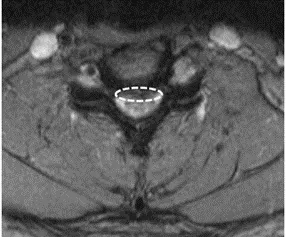

四十多歲的W先生平時從事勞動工作,在COVID-19疫情中仍不斷貢獻自己的勞動力,讓台灣的基礎建設持續運轉,平日的工作總會帶來些許的身體痠痛,但經過休息後多半能緩解。不料最近一個月左上臂、前臂至手掌持續出現麻痛症狀,症狀不分日夜困擾著W先生,甚至嚴重影響夜間睡眠。他求診過地方診所也接受過推拿治療,症狀依然困擾著他,他輾轉來到樂生療養院求診,骨科李元甫醫師在問診及檢查後,懷疑W先生有頸椎椎間盤突出造成頸椎神經根壓迫,後續頸部核磁共振證實W先生有第4/5及5/6兩節的頸椎椎間盤突出壓迫支配左上肢的神經。在數週的藥物配合復健治療下,W先生覺得症狀改善有限,因此在討論過後,W先生決定向公司請假來樂生療養院接受微創頸椎手術。

在等待健保審核衛材的期間,李元甫醫師安排頸椎的硬脊膜外注射,藉此來精準定位受影響的神經根,與此同時W先生也回報左上肢症狀有明顯的緩解。手術採微創方式,在顯微鏡的幫助下精準清除突出的第4/5及5/6兩節的頸椎椎間盤,在確認神經壓迫狀況已解除後放置椎間盤融合器,術後穿戴頸部護具。手術當天即可進食及下床活動,於術後第二天拔除引流管,在確認呼吸、吞嚥及神經學狀況沒有異常後,W先生於隔日辦理出院。